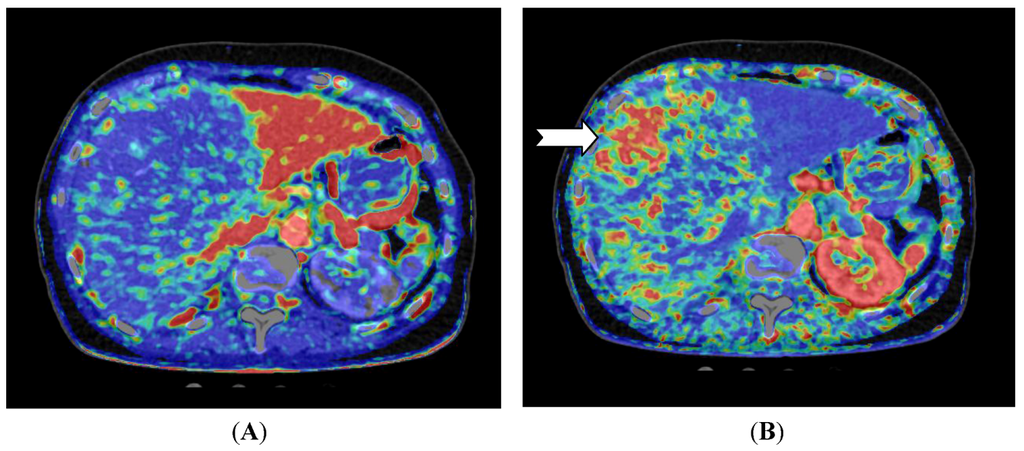

Figure 2.

CT perfusion examination of a 54-year-old male with a solitary hepatocellular carcinoma (HCC) in the right liver lobe (arrow). (A) Perfusion shows high arterial blood supply and (B) lower portal blood supply compared with surrounding normal liver tissue (Images reconstructed with Vitrea 6.2, Vital Images A Toshiba Medical Systems Group).

For liver lesions, Miles et al. [20] first described liver perfusion using CT in 1991 analyzing one 10 mm section. With multidetector CT the entire liver can be covered with a single rotation using a 320-detector row scanner. Applying a dual input—single compartment model provides estimates of both arterial and portal perfusion [38]. Since the first report, several different liver perfusion studies have published. CT perfusion of the liver has demonstrated higher arterial blood flow in cirrhotic patients [39,40] and CT perfusion has been used to characterize hepatocellular carcinoma and to examine for residual tumor after transarterial chemoembolization (TACE) (Figure 2 and Figure 3) [41].